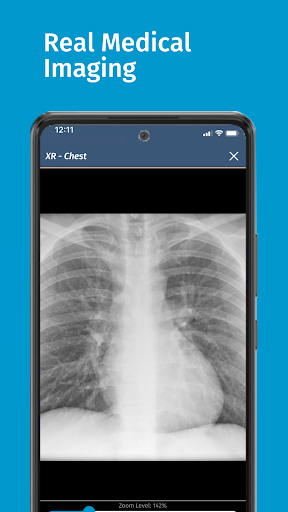

• 200+ thư viện trường hợp được biên soạn và đánh giá bởi các bác sĩ lâm sàng chuyên gia

Được tạo ra bởi các nhà giáo dục y khoa từ một số bệnh viện hàng đầu tại Hoa Kỳ và được các chuyên gia y khoa được cấp phép đánh giá ngang hàng, các mô phỏng của chúng tôi được thiết kế theo các phương pháp thực hành y khoa tốt nhất theo tiêu chuẩn của ngành, đặt ra tiêu chuẩn cao cho sinh viên y khoa và các chuyên gia trên toàn thế giới.